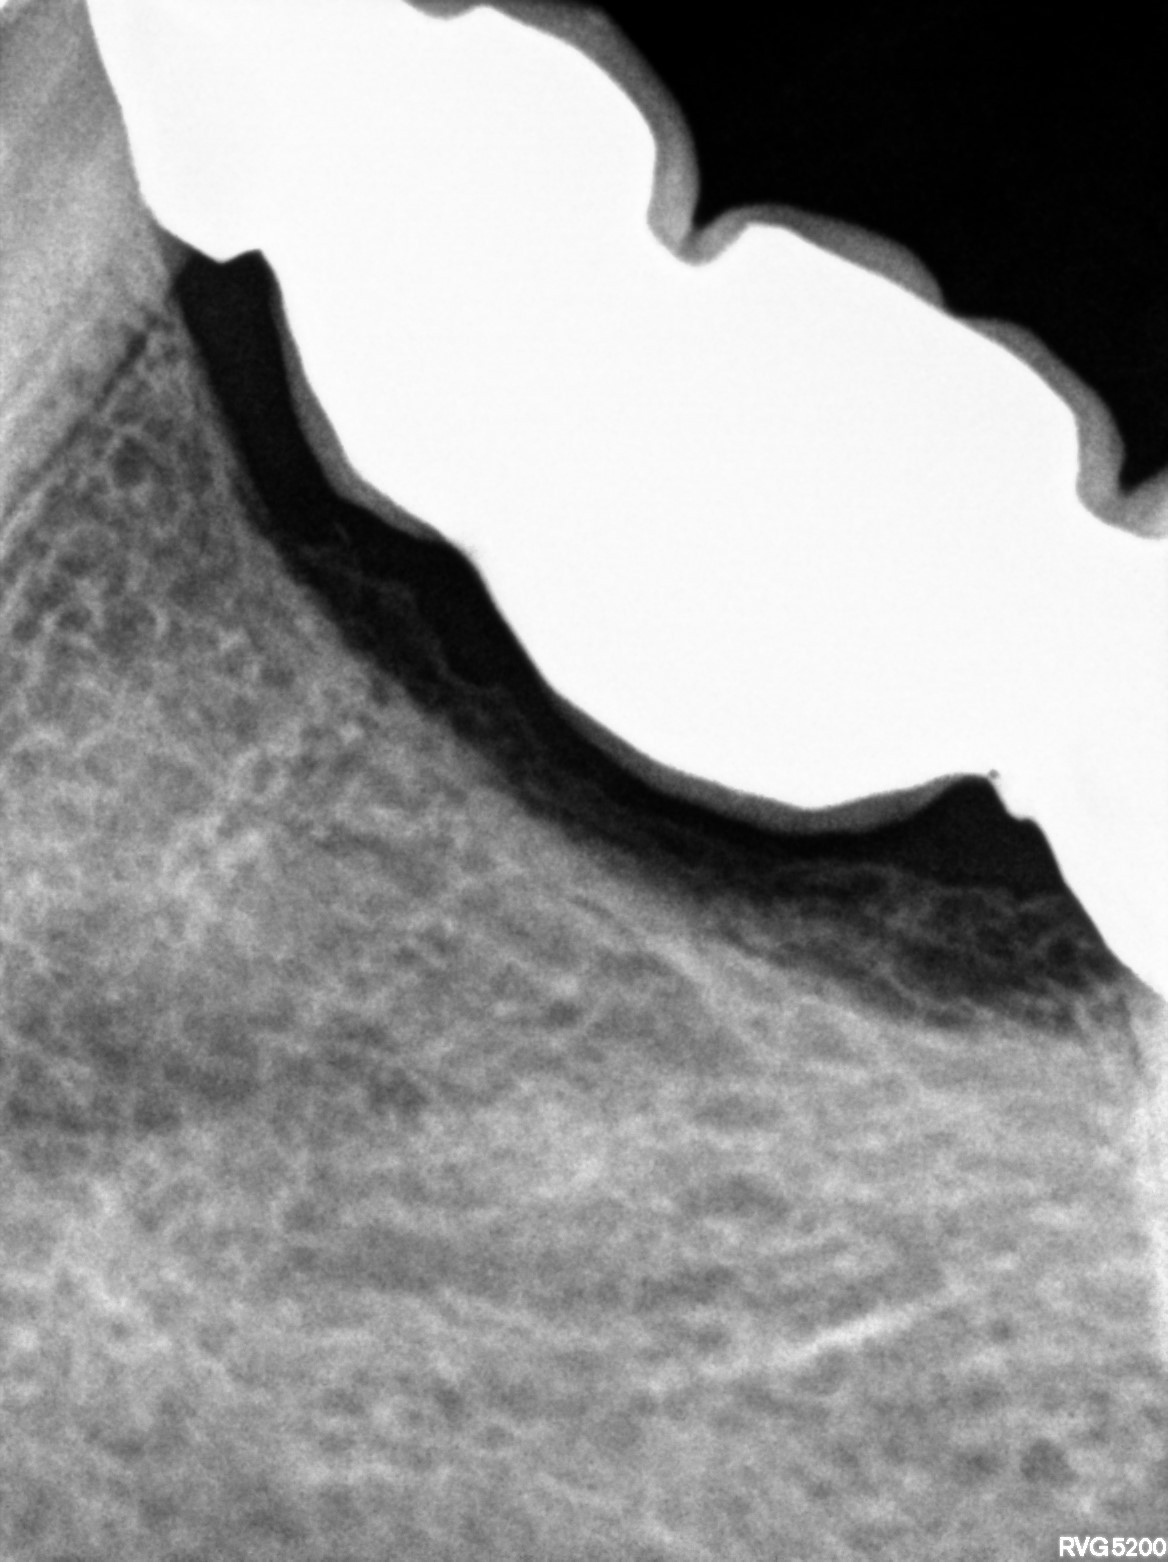

Dental Radiographs FHIR: DocumentReference · LOINC 24641-7

xray_1764234367_1.jpg

24641-7